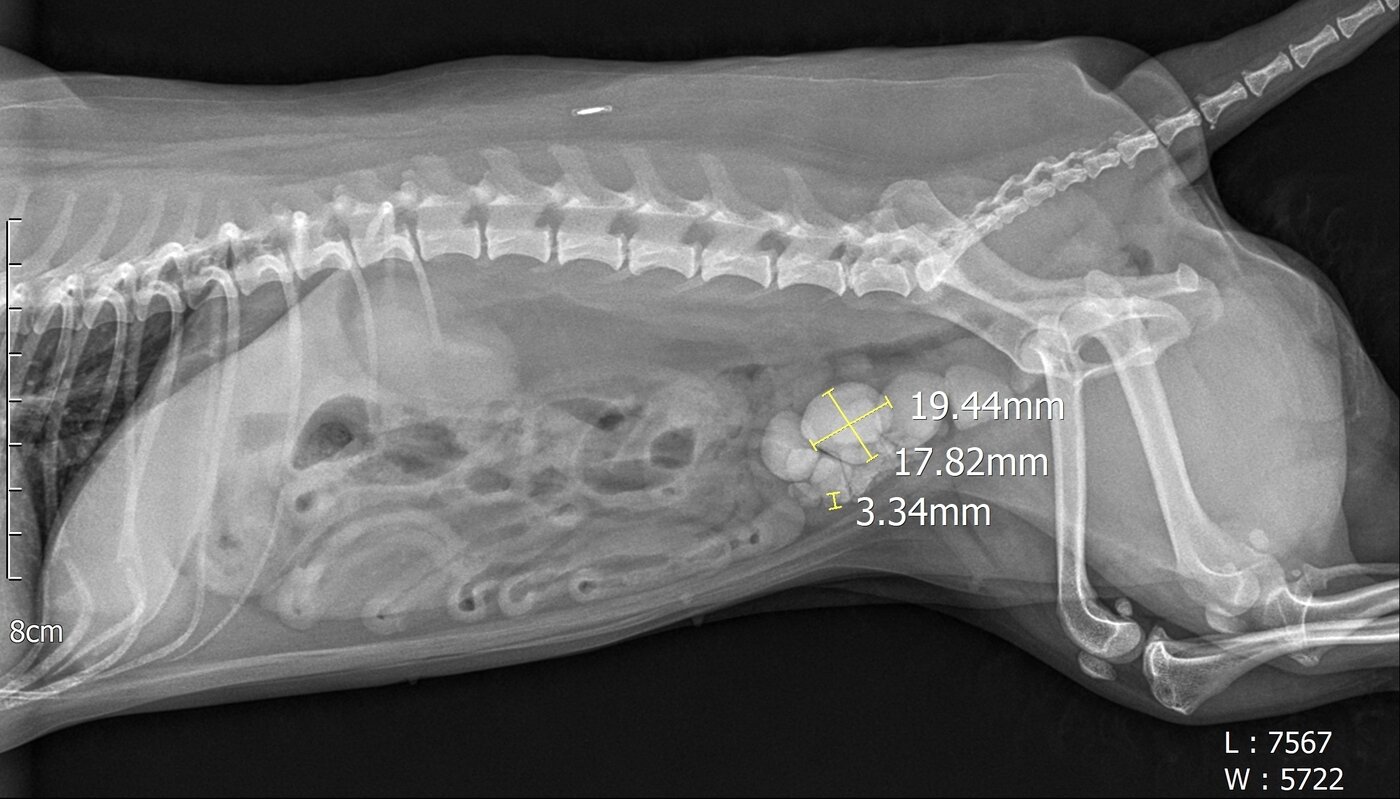

본문 이미지 - 방사선 검사로 확인된 방광결석들(병원 제공) ⓒ 뉴스1

방사선 검사로 확인된 방광결석들(병원 제공) ⓒ 뉴스1